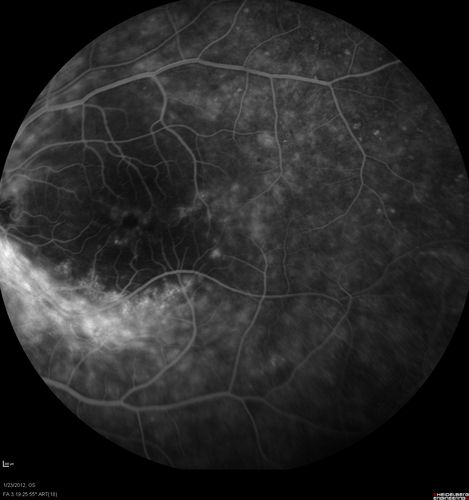

Retinitis Pigmentosa Sine Pigmento or Unknown Dystrophy - Peripheral Superficial White Spots and Recurrent CME

46-year-old woman three of her 5 siblings have been diagnosed with retinitis pigmentosa.  Her mother and father were seen and as far as everyone can tell, neither of them has it, although there was some thought they might be carriers.  They were evaluated twenty five years ago and since then as far as she knows, there has not been a lot of testing done.

She has noticed a substantial decline in vision in both eyes over the last month or two.   OD 20/40,  OS 20/50.   IOP:  Both eyes have CME